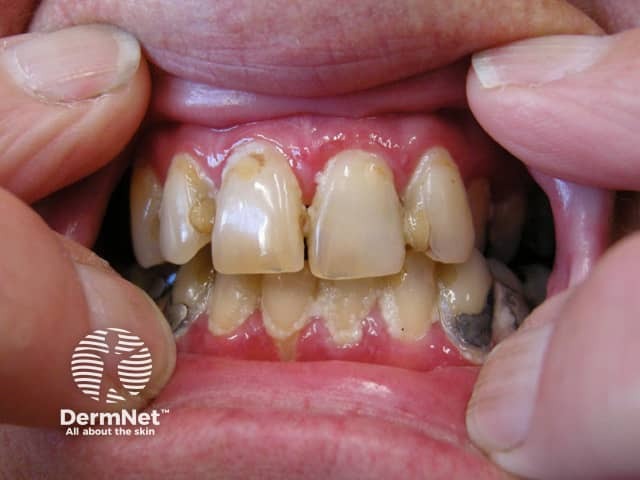

In the mouth, erosions and ulcers may be the only signs (ulcerative stomatitis). They may occur inside the cheeks, on the sides of the tongue, on the gums, or inside the lips. Unlike short-lasting aphthous ulcers, erosive lichen planus lesions are larger and more irregular, and they may persist for weeks or longer. It can be very painful to eat, resulting in weight loss, nutritional deficiencies and depression.

Other forms of oral lichen planus may also occur, including white lacy streaks and inflammation and peeling of the gums (desquamative gingivitis).

Erosive oral lichen planus